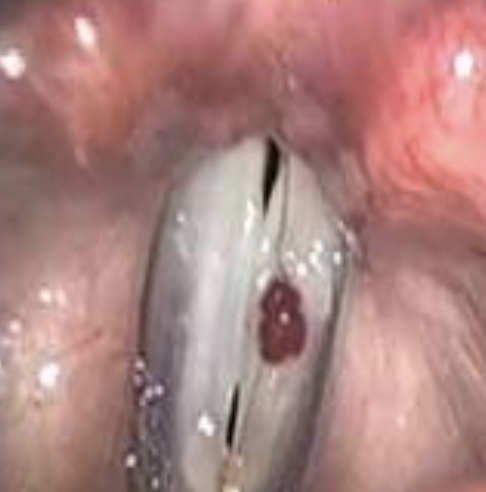

PÓLIPOS

• ANTECEDENTE : ABUSO VOCAL AGUDO

• PATRON UNILATERAL

• PATOLOGIA : LESION PEDICULADA, VASCULARIZADA,

VIOLÀCEA ó ROSA. SÓLO AFECTACIÓN EPITELIAL

• VOZ : BITONAL

Aquí rompe: se queda sangre dentro de cuerda: se organza en forma de hematoma: se transforma en un pólipo. Proceso toma años